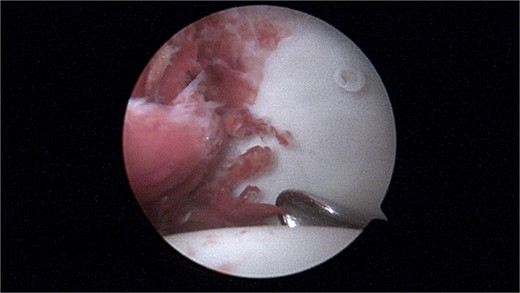

During the arthroscopic procedure, extensive synovial proliferation and a well-defined mass were identified within the joint space. The mass was excised, and the synovium was sampled for histopathological evaluation (Fig. 2). The pathology report confirmed the diagnosis of an SGCT, a rare entity within the hip joint (Fig. 3).

Histopathology showing proliferation of mononuclear synovial cells with oval or polygonal shapes and multinucleated giant cells resembling osteoclasts.